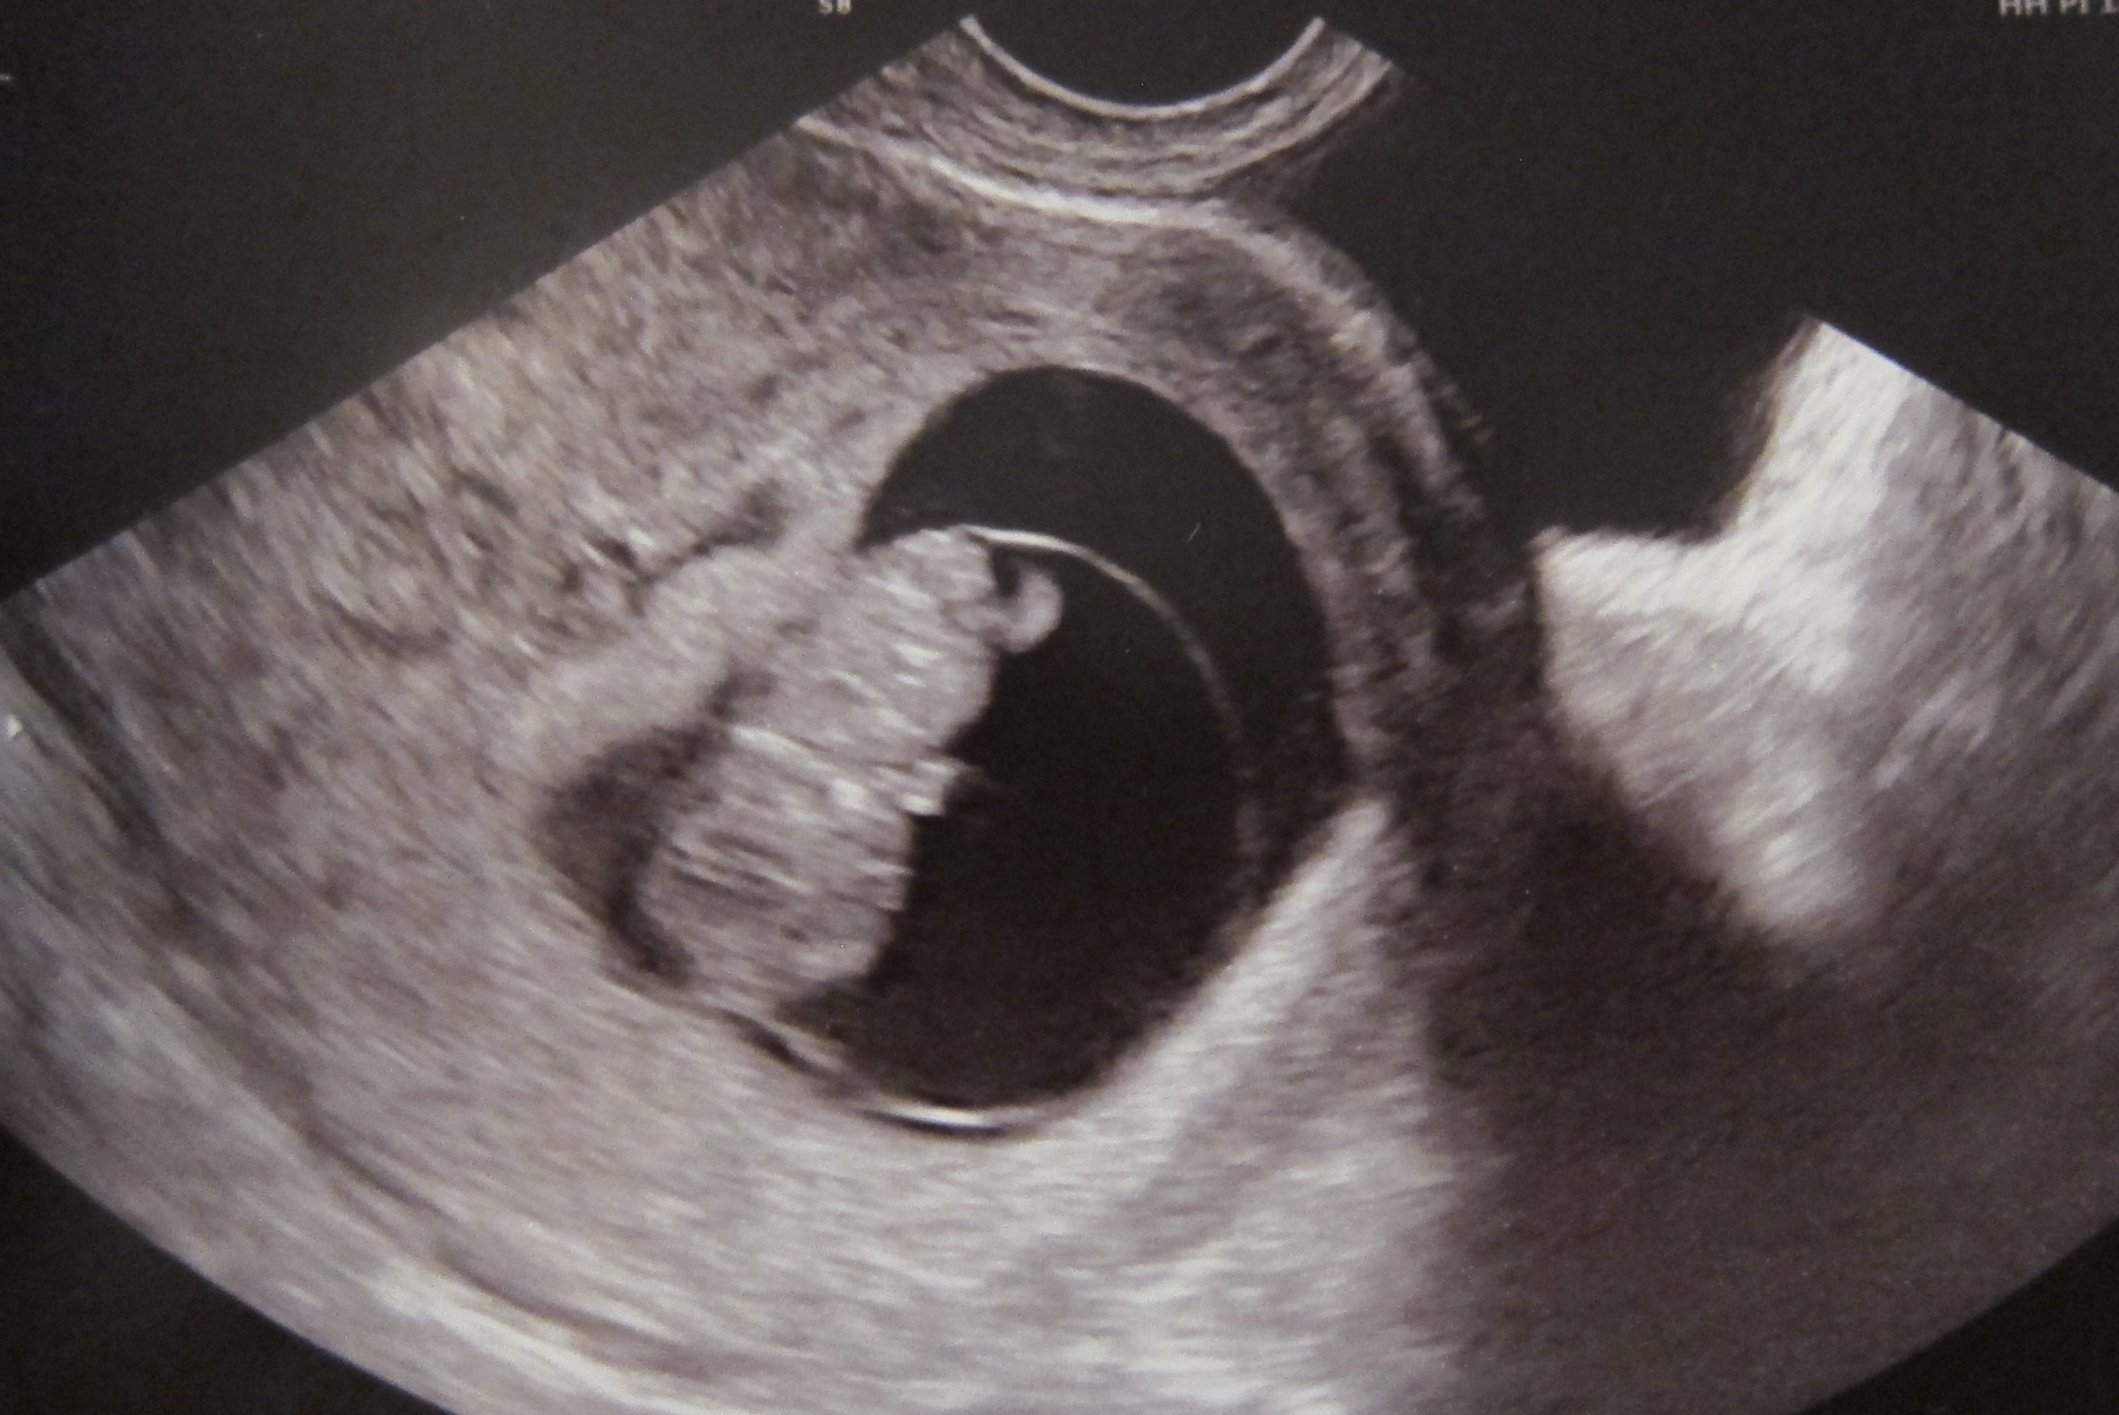

• How far along are you? 8 weeks

How big is baby? Raspberry, peanut M&M

Upcoming appointments this week? Not till next wk for another US

Any new symptoms or changes or cravings? My nausea is starting to not be helped by the Sea Bands which is annoying. I've been craving cereal and bagels which is not a good look for my bloat.

Rants/Raves/Questions?  Rave: my appointment on Friday went well- got to see the gummy bear and measure the HB. It really helped easy my PGAL mind a bit.

GTKY:  What color describes you today? Light pink- bc that was how my body felt being nice and warm snuggling in bed on my day off! (Sorry, @mokay19 :( )